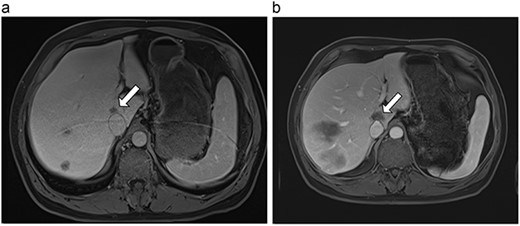

| 1 (3a,b) | 61, F | Colon adenocarcinoma | 6-month FOLFOX | 1 | Laparoscopic microwave ablation | 6 | 40.4 | 34.4 | 10 | No |

(a) Pre-ablation MRI demonstrates 6 mm lesion in caudate lobe of liver. (b) Post-ablation MRI (18 days postoperatively) demonstrates 40.4 mm complete ablation site in caudate lobe of liver.